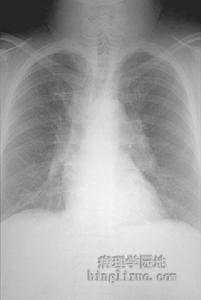

除神經系統損害的表現外還可有皮膚淋巴結、肺及其他臟器受累的表現可表現有皮膚結節樣紅斑隆起淋巴結腫大、咳嗽、咳痰及咯血等。

2.腦血管造影大多正常,僅偶爾有血管炎健的表現腦CT常表現有病變區密度勱的輕度增高,經造影劑強化後病變呈均一強化,周圍可出現水腫帶。MRI對神經系統結節病的診斷具有較高敏感性可顯示腦室周圍白質有T2加權的高信號變化T1加權像呈多種信號混雜有腦膜病變時,強化掃描可發現腦膜強化。3.放射性核素67鎵(67Ga)掃描對結節病診斷價值較高可早期發現肺部病灶有學者認為67Ga掃描與血清血管緊張素Ⅰ轉換酶兩者的結合對結節病的診斷準確率為80%~90%。4.腦膜和腦組織或周圍神經的活檢可明確診斷。